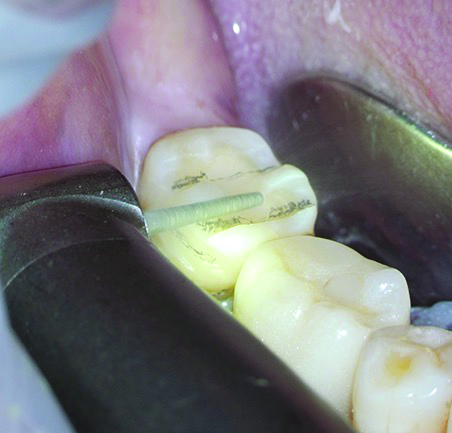

The next clinical step emphasizes the collaborative effort of the clinician and in-house technician to ensure a high-quality preparation design through digital scanning verification. In this critical process, the technician works alongside the clinician to thoroughly review every detail of the preparation zone on the digital scan while simultaneously applying necessary intraoral corrections under the DOM (Figure 9). Using an intraoral scanner, a highly precise digital impression is recorded, not only for converting the prepared tooth into a virtual model but also to facilitate teamwork within the clinic. This real-time collaboration allows the clinician to receive immediate feedback from the  technician, prompting on-the-spot improvements in preparation quality.

Fig 9. The clinician (left) was accompanied by the in-house technician for the scanning process to check every detail together and apply intraoral corrections microscopically if necessary.

Figure 9